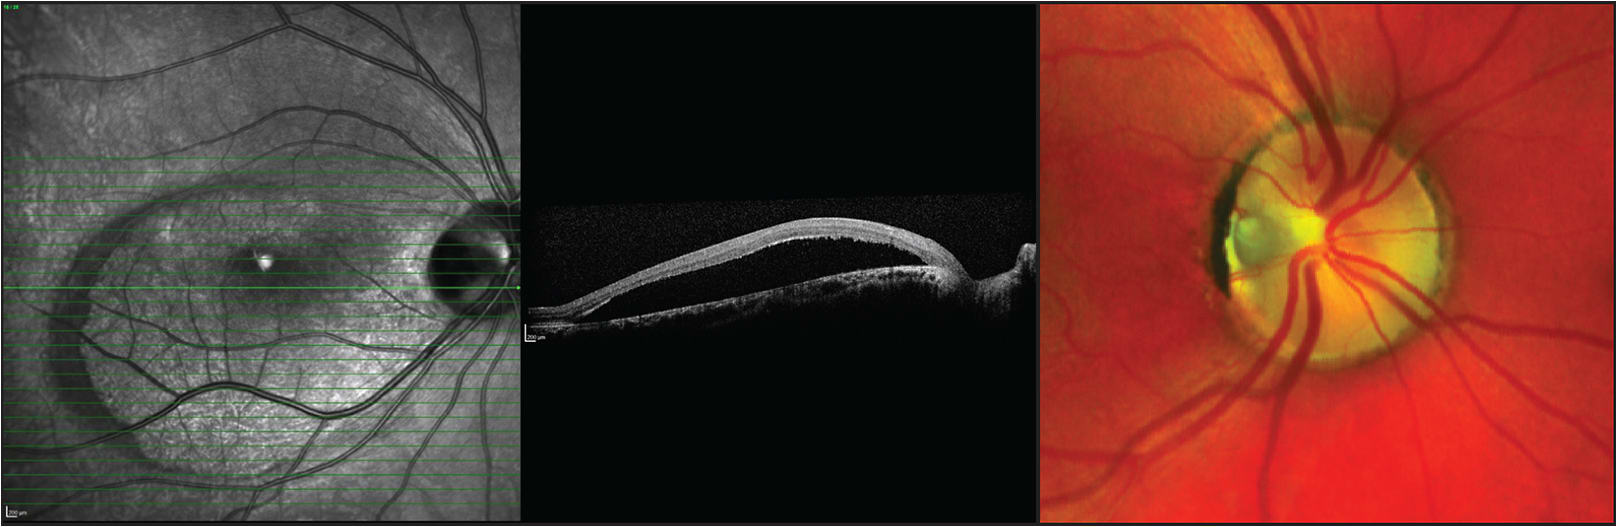

In isolation, ODPs are often asymptomatic; however, they may go on to develop an associated neurosensory detachment of the macula (Figure 1), with subsequent reduction in vision. This maculopathy occurs in 25% to 75% of patients with ODPs,3,4 and it usually occurs in the third to fourth decade of life.5

Figure 1. Images of a patient with optic disk pit maculopathy. The pit size may be from one-eighth to half the diameter of the optic disk. There is a neurosensory detachment of the fovea.

This theory is supported by spontaneous resolution of fluid with the development of a posterior vitreous detachment and by the evidence of a direct connection between the subretinal space of the macula and the ODP on optical coherence tomography (Figure 2).

Figure 2. ODP maculopathy. Note the connection between the subretinal space and ODP on optical coherence tomography.